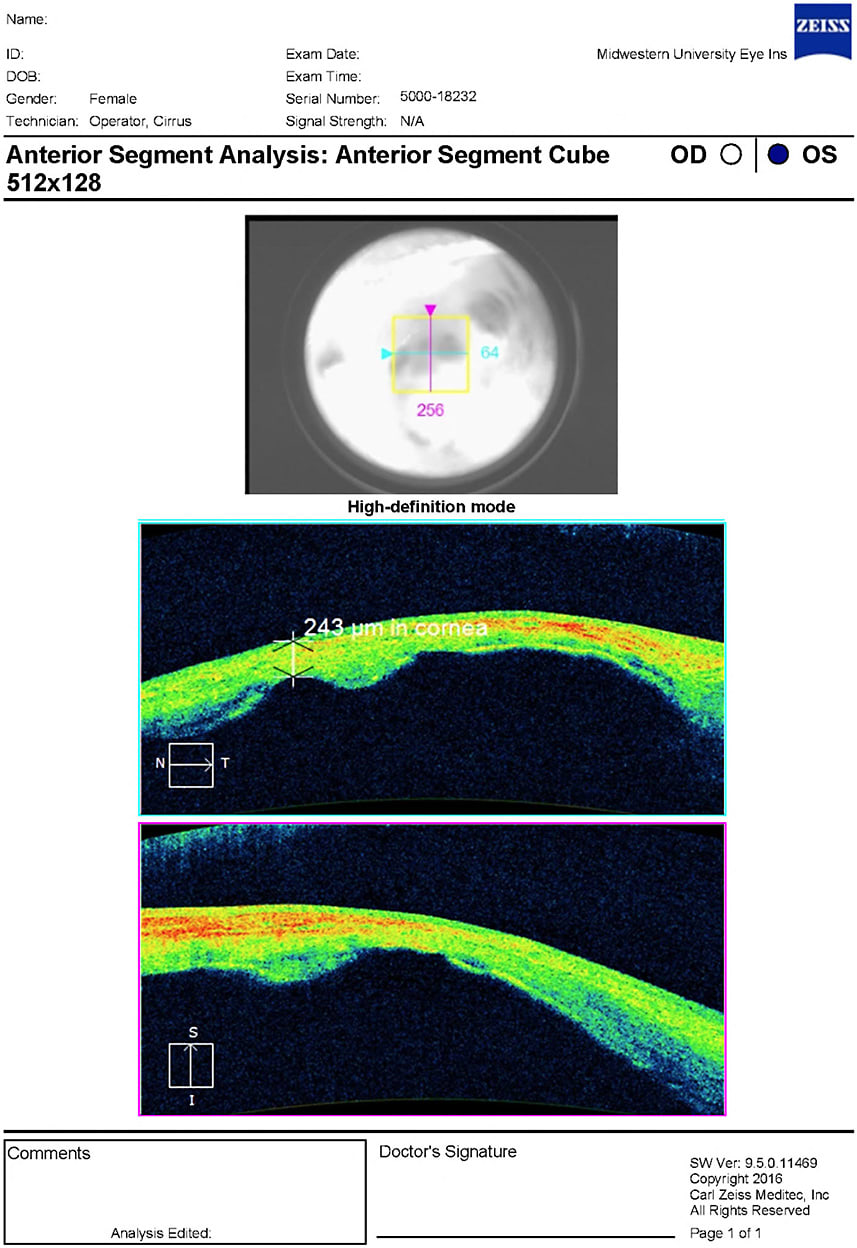

All testing for OD revealed normal findings with 20/20 uncorrected visual acuity. OS had no light perception with 4+ afferent pupillary defect (APD). Severe vascularized opacification was found on the OS cornea with multiple areas of elevation and uveal show. A tube shunt was observed superior nasally, but unable to assess patency. The intraocular pressure was 13 mmHg and 20 mmHg for OD and OS, respectively. Dilated fundus examination for OS was not able to be viewed. B-scan ultrasonography was performed and found vitreous degeneration with a grossly flat retina.

Figures 1 and 2 show the patient in primary and downgaze, respectively. Figures 3 and 4 demonstrate the corneal staphyloma using anterior segment optical coherence tomography. This patient was diagnosed with corneal staphyloma and minor scleromalacia secondary to surgical complications from fetal alcohol syndrome. She deferred enucleation and/or ocular prosthetic consult.